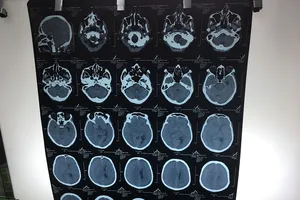

BV quận 11 mổ thành công chấn thương sọ não